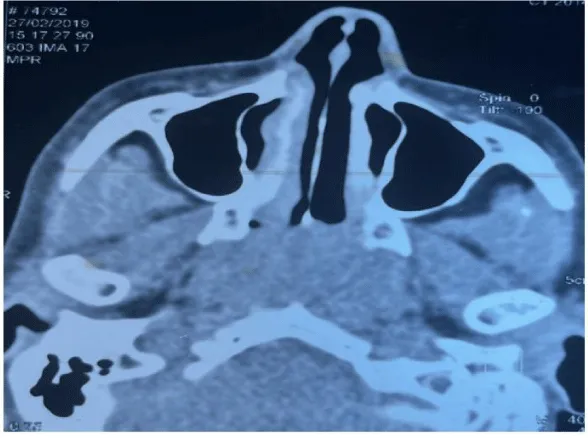

The CT scan revealed the filling of the entire cavum by a tissue process (Figure 1), as well as bilateral axillary and supra-clavicular adenopathies.

Control CT was normal 6 months after chemotherapy (Figure 2). A follow-up panendoscopy revealed a budding mass in the right Rosenmüller fossa and the roof of the cavum. Pathological examination revealed the absence of lymphomatous proliferation.